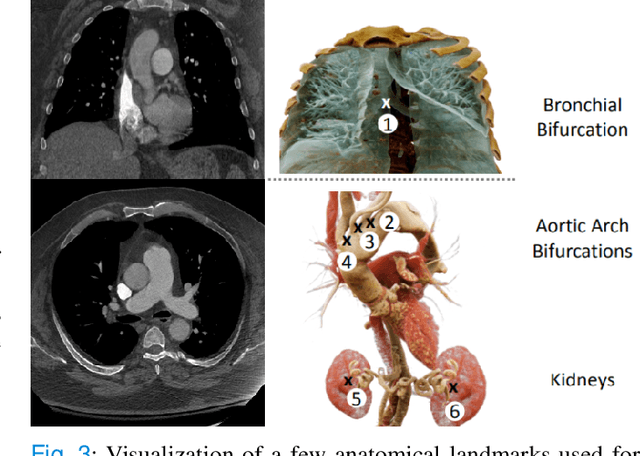

Pulmonary Embolisms (PE) represent a leading cause of cardiovascular death. While medical imaging, through computed tomographic pulmonary angiography (CTPA), represents the gold standard for PE diagnosis, it is still susceptible to misdiagnosis or significant diagnosis delays, which may be fatal for critical cases. Despite the recently demonstrated power of deep learning to bring a significant boost in performance in a wide range of medical imaging tasks, there are still very few published researches on automatic pulmonary embolism detection. Herein we introduce a deep learning based approach, which efficiently combines computer vision and deep neural networks for pulmonary embolism detection in CTPA. Our method features novel improvements along three orthogonal axes: 1) automatic detection of anatomical structures; 2) anatomical aware pretraining, and 3) a dual-hop deep neural net for PE detection. We obtain state-of-the-art results on the publicly available multicenter large-scale RSNA dataset.